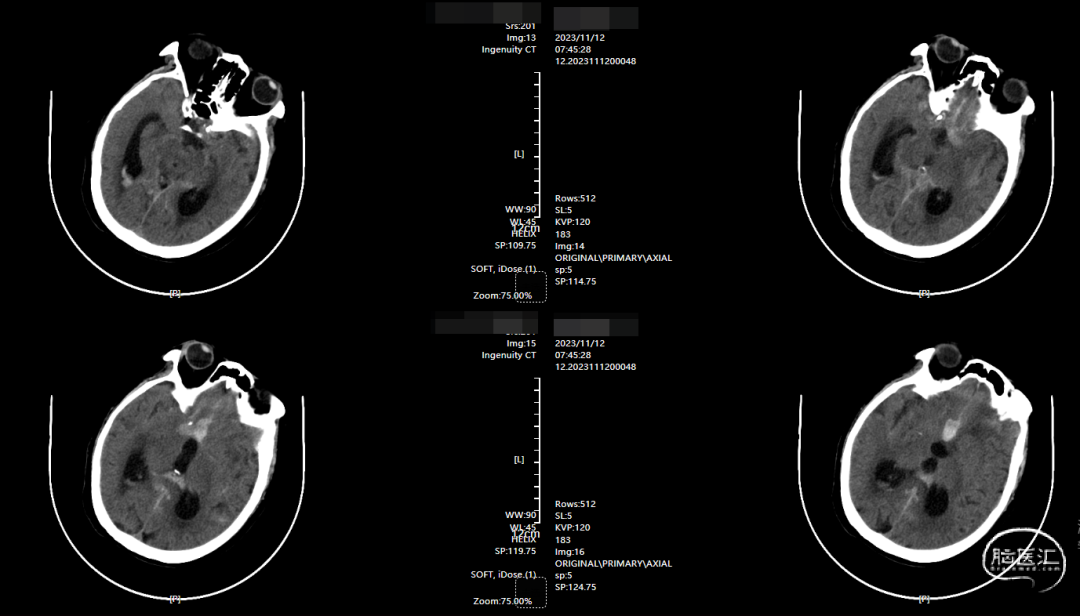

术前影像

CT示纵裂内血肿。